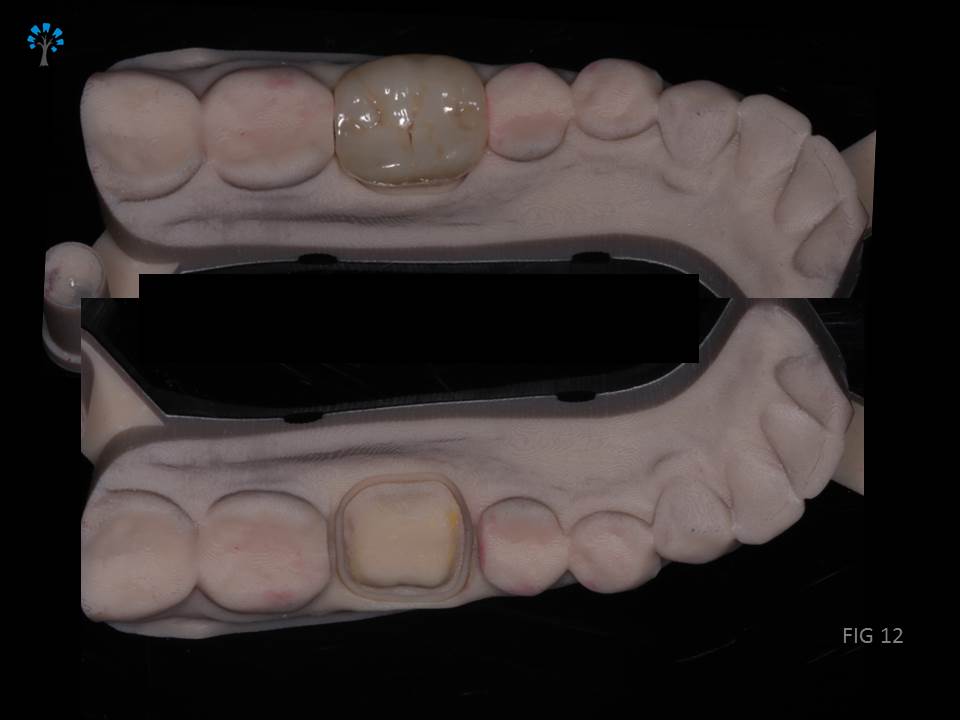

Monolithic EMAX crown was fabricated (KATARA DENTAL, PUNE) and bonded.(Fig 10 -12)